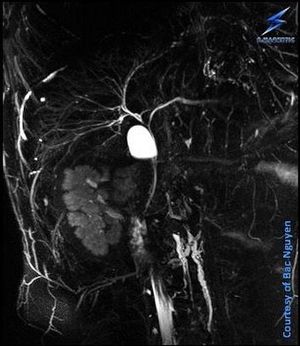

MRCP – Prone Positioning @ Siemens AvantoFit 1.5T Have you tried MRCP where patient lie on the stomach (prone positioning). This is something we routinely don’t do, but I know sites where they do this. Just had to try. I don’t see any pitfalls in this, do you? Besides, this approach doesn’t fit every patients I guess. It might help towards respiratory artifacts, any cons? #smagnetic #siemens #MRI #MRCP